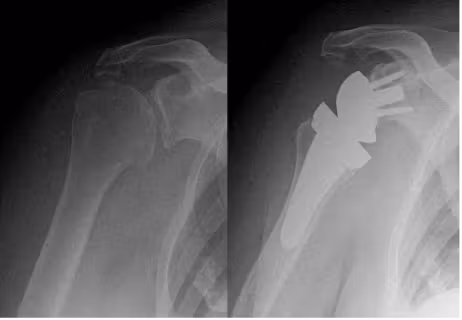

上肢人工関節は下肢関節とは違い体重のかからない関節ですので、痛みをとるだけではなく関節の動きを改善し、関節の機能をよくする目的で手術を行っております。関節軟骨が破壊された部位を切除し人工関節に置き換えます。腱板の機能が温存されている場合は、解剖学的な人工関節を選択し、腱板機能不全の患者様に対しては反転型の人工肩関節を用い機能改善を目指しております。

腱板断裂性関節症に対する人工肩関節置換術(反転型)